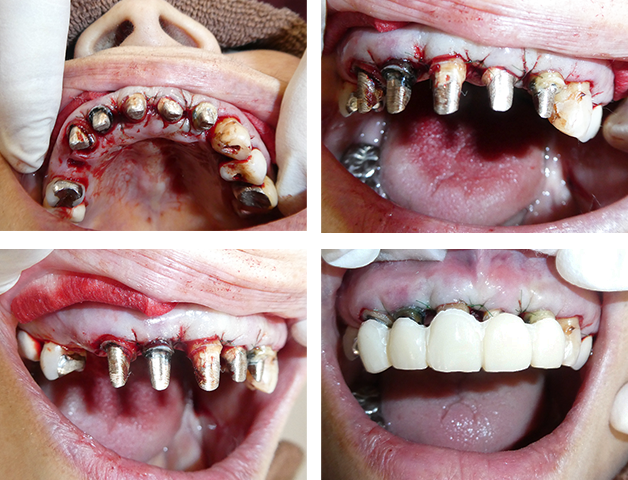

歯周外科治療の症例

1-

術前写真

初診時の口腔内写真です。全体的に歯周病の進行がひどく、上顎のやりかえ治療を希望で来院されました。

右上1番は骨欠損、動揺がひどく残すのも厳しい状態でしたが、歯周外科手術を行い、なんとか保存していく治療計画で進めました。

このケースは、ひとまず下顎には手をつけず上顎の治療を進めていきたいとの希望でした。

2-

術中写真

歯周外科手術中の写真です。前歯部に深い骨欠損があることがわかります。再生療法を併用して骨の回復を期待します。

3-

術直後写真

手術の直後も食事、見た目に支障がないように仮歯の調整を行います。手術部位との隙間も歯肉の回復を待って隙間の調整をしていきます。

4-

治癒経過写真

歯肉が回復してきて、歯の動揺も治まってきました。深い歯周ポケットも正常値まで改善が認められます。

5-

術後写真

上顎の治療終了後写真です。右上4番の欠損部位にはインプラントを1本埋入して歯列を回復しています。